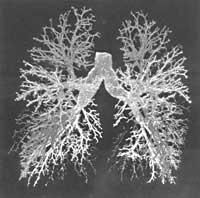

El humo del tabaco es una mezcla compleja de miles de compuestos, pero la nicotina produce los efectos más inmediatos sobre el cuerpo del fumador y a la vez la adicción al cerebro y al comportamiento. Sin embargo, el cáncer de pulmón se debe a las sustancias llamadas alquitrán o alquitrán que se encuentran en el humo y a otras enfermedades. Por lo tanto, se pueden distinguir los elementos que producen el efecto buscado por los fumadores de los que producen daño físico. Podemos preparar medidas para minimizar los daños derivados de la combustión y así ayudar a que la gente deje de fumar.

Para comprender la adicción a la nicotina, es necesario saber cómo la persona actúa en el cerebro para crear un refuerzo positivo tan influyente cuando fuma, para actuar como “eficaz” y provocar el efecto contrario. También necesitamos comprender los cambios de adaptación que se producen en el cerebro en el síndrome de abstinencia de la nicotina. Tras el descubrimiento en el cerebro de los receptores de la nicotina, el interés por la dependencia de la nicotina se ha disparado en la década pasada. A mediados de la década de 1970 se utilizaban drogas nicotínicas para identificar la adhesión de la nicotina a los receptores en las membranas externas a las células cerebrales.